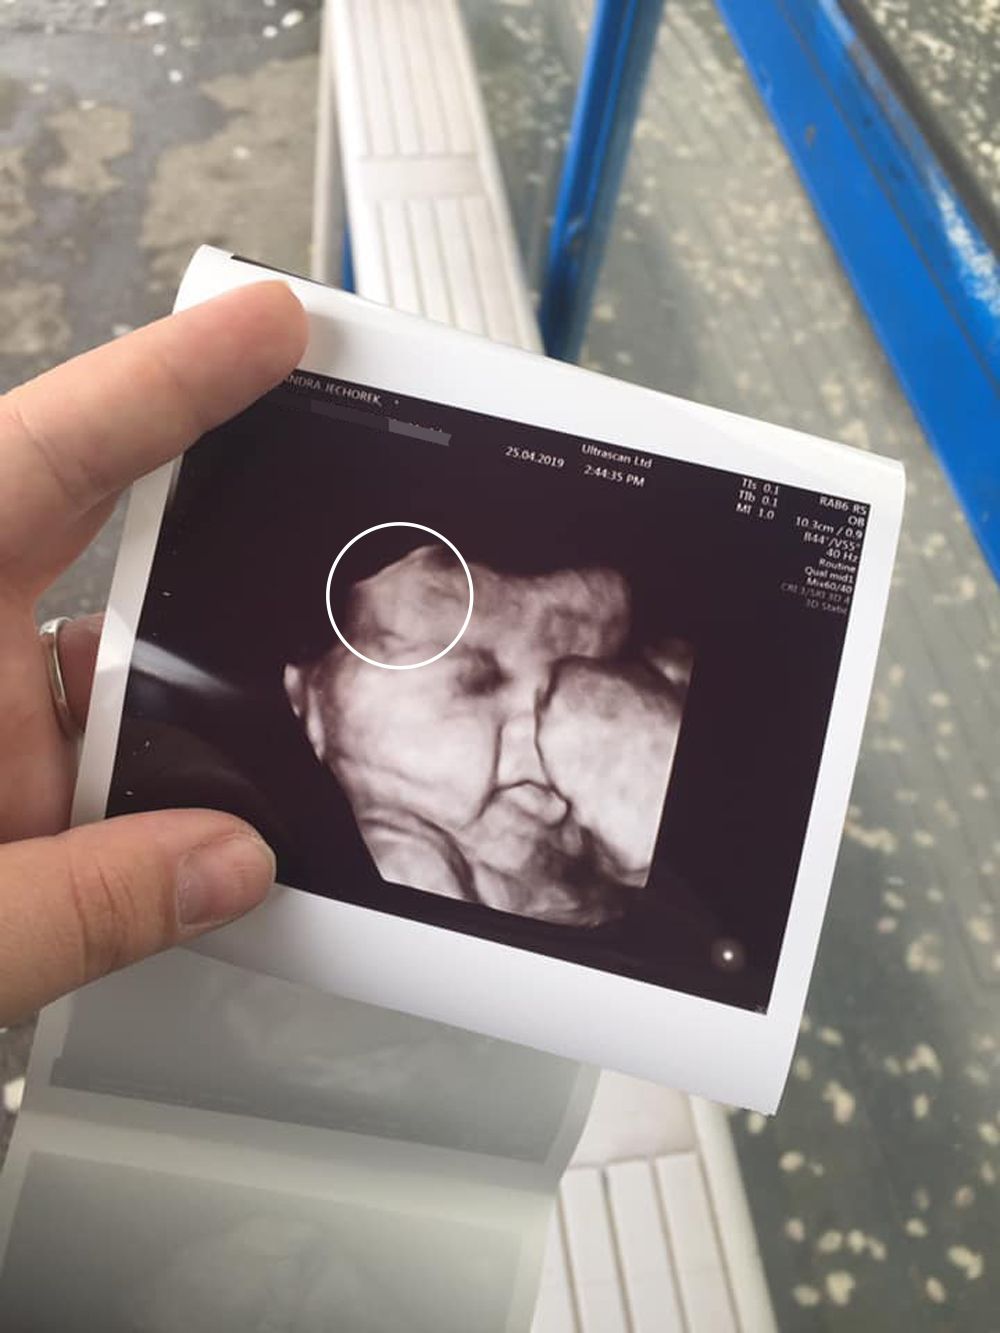

This mom recalled her shock when she realized her baby girl already had hair in the womb. Which was clearly visible at her 34 week scan.

“We'd already found out we were expecting a girl at the previous scan, so at 34 weeks, we were just excited to see how much she'd grown," she said.

“When the midwife turned the screen around, I honestly couldn't believe my eyes. There was this tiny little baby on the scan with a full head of hair. I just thought, 'No way, this cannot be possible'."